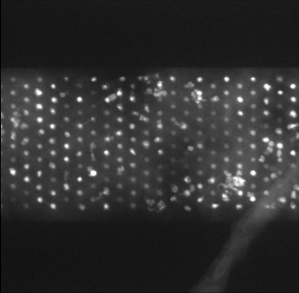

• [ZXSE07] Noha El Zehiry, Steve Xu, Prasanna Sahoo, and Adel Elmaghraby. Graph cut optimization for the Mumford-Shah model. In VIIP ’07 The Seventh IASTED International Conference on Visualization, Imaging and Image Processing, pages 182–187, 2007.